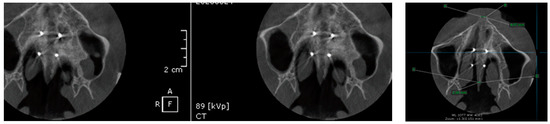

- MARPE associated with cortico-puncture therapy efficiently split the midpalatal suture in adults. The mean split at the anterior nasal spine (ANS) and posterior nasal spine (PNS) was 3.76 and 3.12 mm, respectively. The magnitude of the split at the PNS was smaller than at the ANS (by approximately 85% of the distance), showing that the opening of the midpalatal suture was almost parallel in the anteroposterior direction.

- Our results suggest that non-surgical palatal expansion, assisted by micro-implants and cortico-puncture, is achievable and predictable in young adults. This occurs in safe conditions without the need for more complex surgical treatment.

- The combination of MARPE and the cortico-puncture method proved to be a non-surgical treatment option to correct maxillary transverse deficiency in young adult patients. Cortico-puncture was able to weaken the suture interdigitation, thus facilitating the split.